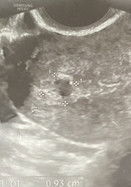

sub chorionic hemorrhage

meron po ba ditong may ganyang findings sa trans v, nagproceed naman po ang pregnancy niyo? 4-5 weeks gestational sac pa lang based sa trans v. thanks!